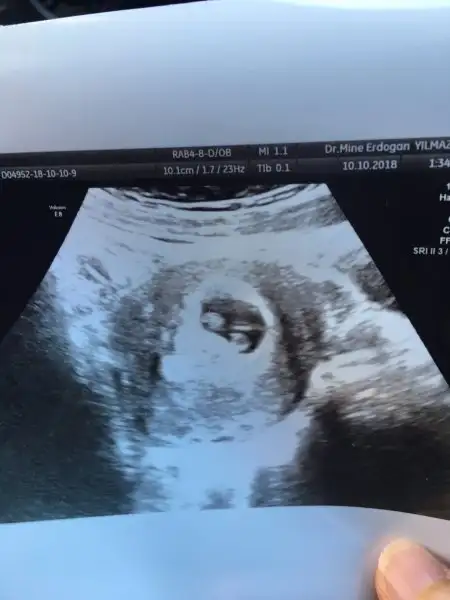

Seninkisi tek canim bos gorulen kisim embriyo degil kese boslugu diye dusunuyorum. Ama ikiz olamasini isterim topikte tekim (

Bir kişi daha vardı sanırım ya ikiz öyle hatırlıyorum. Banada benimki tek geliyor boş kısımda göremiyorum ben yatan bi bebek görüyorum başı ve gövdesi olan bak bida atıyım iyice bakın uzanıyor resmen sol taraftaki başı devamındaki ayağı bacağı